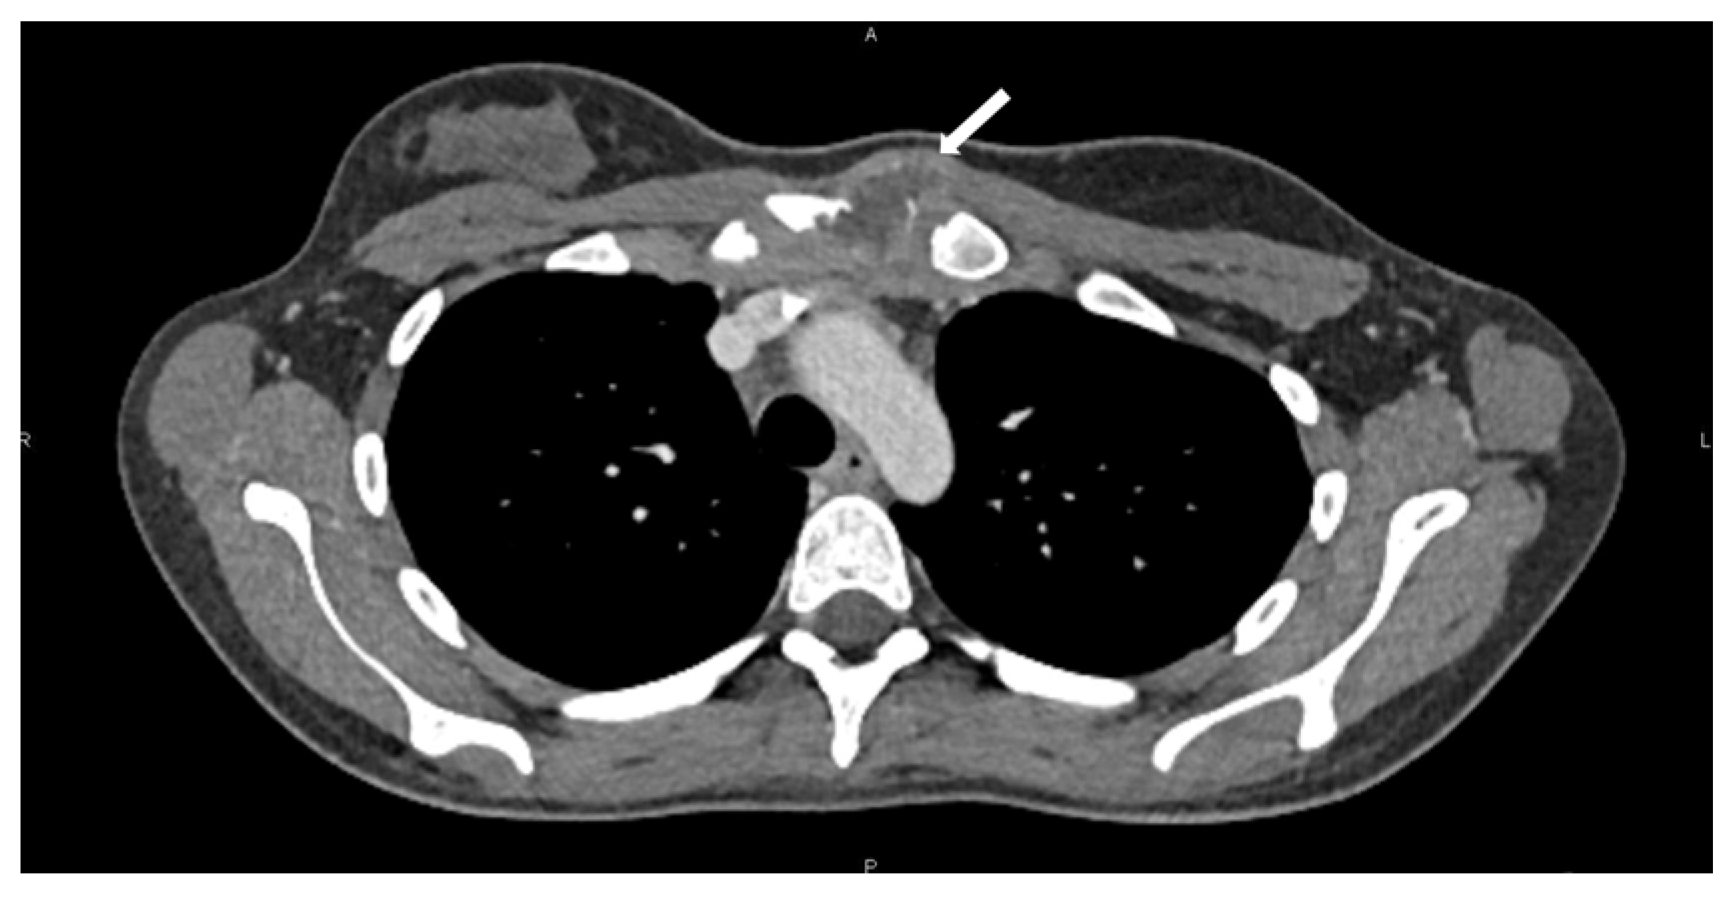

A 19-year-old woman presented with progressive pain and swelling over the left SCJ following minor upper extremity trauma. CT imaging of the neck and chest revealed a 39 × 28 mm lesion involving the left hemimanubrium, medial clavicle, and first costal cartilage with soft tissue extension. PET-CT demonstrated intense uptake (SUVmax 7). A CT-guided biopsy confirmed a poorly differentiated (G3) chondrosarcoma. No distant metastases were identified (Figure 1). The patient received six cycles of neoadjuvant chemotherapy consisting of four cycles of high-dose methotrexate and two cycles of cisplatin (CDP)-docorubicin (ADM), which resulted in the radiological stability of the lesion. Restaging imaging showed that the tumor remained localized to the manubrium with limited invasion of adjacent structures, and the case was discussed on a multidisciplinary tumor board. Surgical resection was then planned. The decision to proceed with surgery rather than additional systemic therapy was based on multidisciplinary consensus and the limited expected benefit of further cytotoxic treatment in high-grade chondrosarcoma. The lesions’ location and involvement of the SCJ required preoperative planning that was equally focused on oncologic clearance and the restoration of clavicular stability.

Figure 1. Preoperative CT scan showing the lesion (white arrow) involving the left hemimanubrium, medial clavicle, and first rib.